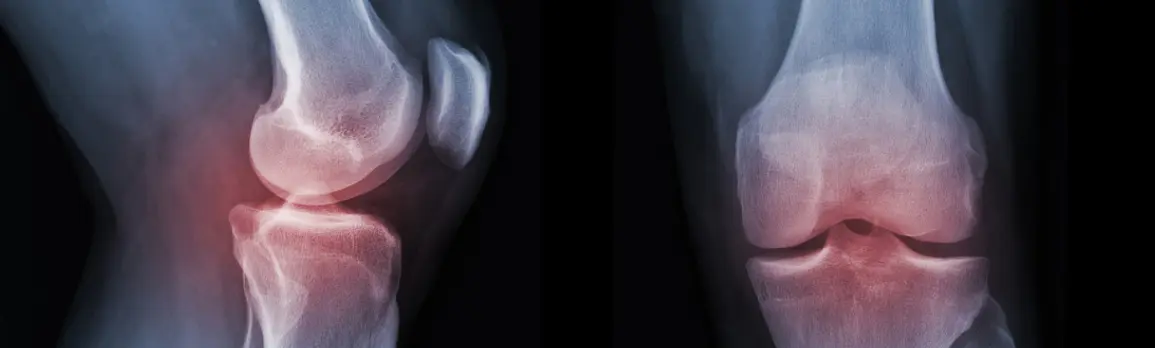

リウマチ登録医による早期発見、早期治療を行いリウマチの進行を抑え、早期リハビリテーションを行い日常生活を送れる事を目標に行っています。また、進行例に対しては人工関節手術も随時行っています。